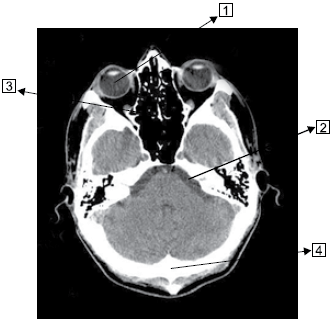

Observe a imagem a seguir.

Assinale a alternativa que corresponde às estruturas identificadas na imagem.